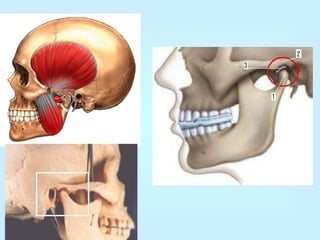

Articulación Temporomandibular Es la  articulación  entre el  hueso temporal  y la  mandíbula .  Son dos articulaciones, una a cada lado de la  cabeza , que funcionan sincrónicamente. Es la única articulación móvil entre los huesos de la cabeza.

Sección sagital de la ATM. Pueden verse el cóndilo de la mandíbula (proceso posterior de la rama ascendente) y el cóndilo del temporal. En medio, el menisco articular.       Vista lateral mostrando, de izquierda a derecha, el ligamento estilomaxilar, la cápsula articular, el ligamento esfenomaxilar y el ligamento pterigomaxilar. Representadas por el cóndilo de la mandíbula y por la cavidad glenoidea y el cóndilo del temporal. Cóndilo mandibular : Eminencia elipsoidea situada en el borde superior de la rama ascendente de la mandíbula, a la que está unida por un segmento llamado cuello del cóndilo. La superficie articular tiene dos vertientes: Una anterior, convexa, que mira arriba y adelante y otra posterior, plana y vertical.  El  Tubérculo articular  y la  Fosa mandibular  representan las superficies articulares del temporal, en correspondencia con la de la mandíbula. La cavidad glenoidea se encuentra dividida en dos zonas, separadas por la una unidad anatómica y funcional. Sistema ligamentoso  [ editar ]

4 Movimientos de la ATM   4.1 Movimientos de descenso y elevación   4.2 Movimientos de proyección hacia delante y hacia atrás   4.3 Movimientos de  lateralidad  o  diducción   5 Músculos de la ATM   6 Bibliografía   Generalidades  [ editar ] La ATM (Articulación Temporomandibular) está compuesta por un conjunto de estructuras anatómicas que, con la ayuda de grupos  musculares  específicos, permite a la mandíbula ejecutar variados movimientos aplicados a la función masticatoria (apertura y cierre, protrusión, retrusión, lateralidad). Existe, además, una articulación  dentaria  entre las piezas de los dos maxilares, que mantiene una relación de interdependencia con la ATM: Cualquier trastorno funcional o patológico de localización en cualquiera de ellas será capaz de alterar la integridad de sus respectivos elementos constitutivos. (A veces se habla de  Articulación Temporomandibulodentaria ) La ATM está formada por el cóndilo de la mandíbula, con la cavidad glenoidea y el cóndilo del hueso temporal. Entre ellos existe una almohadilla fibrosa: Disco articular. Por encima y por debajo de este disco existen pequeños compartimentos en forma de saco denominados cavidades sinoviales. Toda la ATM está rodeada de una cápsula articular fibrosa. La cara lateral de esta cápsula es más gruesa y se llama  ligamento  temporomandibular, evitando que el cóndilo se desplace demasiado hacia abajo y hacia atrás, además de proporcionar resistencia al movimiento lateral. Los cóndilos temporal y mandibular son los únicos elementos activos participantes en la dinámica articular por lo que se considera a esta articulación una  Diartrosis bicondílea .

Articulación Temporomandibular Esla articulación entre el hueso temporal y la mandíbula . Son dos articulaciones, una a cada lado de la cabeza , que funcionan sincrónicamente. Es la única articulación móvil entre los huesos de la cabeza.

Sección sagital dela ATM. Pueden verse el cóndilo de la mandíbula (proceso posterior de la rama ascendente) y el cóndilo del temporal. En medio, el menisco articular. Vista lateral mostrando, de izquierda a derecha, el ligamento estilomaxilar, la cápsula articular, el ligamento esfenomaxilar y el ligamento pterigomaxilar. Representadas por el cóndilo de la mandíbula y por la cavidad glenoidea y el cóndilo del temporal. Cóndilo mandibular : Eminencia elipsoidea situada en el borde superior de la rama ascendente de la mandíbula, a la que está unida por un segmento llamado cuello del cóndilo. La superficie articular tiene dos vertientes: Una anterior, convexa, que mira arriba y adelante y otra posterior, plana y vertical. El Tubérculo articular y la Fosa mandibular representan las superficies articulares del temporal, en correspondencia con la de la mandíbula. La cavidad glenoidea se encuentra dividida en dos zonas, separadas por la una unidad anatómica y funcional. Sistema ligamentoso [ editar ]

4 Movimientos dela ATM 4.1 Movimientos de descenso y elevación 4.2 Movimientos de proyección hacia delante y hacia atrás 4.3 Movimientos de lateralidad o diducción 5 Músculos de la ATM 6 Bibliografía Generalidades [ editar ] La ATM (Articulación Temporomandibular) está compuesta por un conjunto de estructuras anatómicas que, con la ayuda de grupos musculares específicos, permite a la mandíbula ejecutar variados movimientos aplicados a la función masticatoria (apertura y cierre, protrusión, retrusión, lateralidad). Existe, además, una articulación dentaria entre las piezas de los dos maxilares, que mantiene una relación de interdependencia con la ATM: Cualquier trastorno funcional o patológico de localización en cualquiera de ellas será capaz de alterar la integridad de sus respectivos elementos constitutivos. (A veces se habla de Articulación Temporomandibulodentaria ) La ATM está formada por el cóndilo de la mandíbula, con la cavidad glenoidea y el cóndilo del hueso temporal. Entre ellos existe una almohadilla fibrosa: Disco articular. Por encima y por debajo de este disco existen pequeños compartimentos en forma de saco denominados cavidades sinoviales. Toda la ATM está rodeada de una cápsula articular fibrosa. La cara lateral de esta cápsula es más gruesa y se llama ligamento temporomandibular, evitando que el cóndilo se desplace demasiado hacia abajo y hacia atrás, además de proporcionar resistencia al movimiento lateral. Los cóndilos temporal y mandibular son los únicos elementos activos participantes en la dinámica articular por lo que se considera a esta articulación una Diartrosis bicondílea .